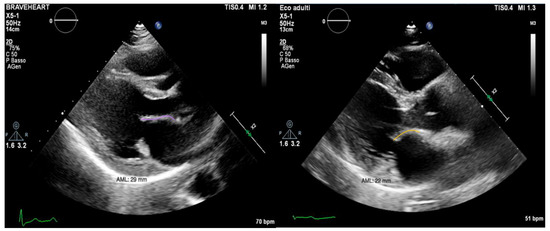

In conclusion, the variables that were identified as the predictors of major arrhythmic events with the highest AUC (>0.80) within our high-risk population of arrhythmic MVP patients were the AML length (measured as shown in Figure 7), the S3 of the inferolateral basal segment and the mechanical dispersion of the basal and mid-ventricular segments calculated with speckle tracking analysis (Figure 8 and Figure 9).

Figure 7. On the left, PLAX (parasternal long axis) view of a patient from the ICD-MVP group, with a longer AML (anterior mitral leaflet) (29 mm). On the right, PLAX view of a patient from the A-MVP group, with a shorter AML (22 mm).